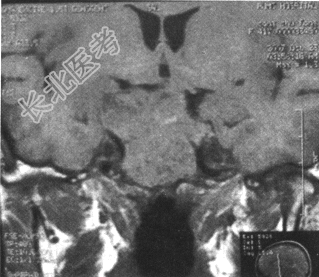

鞍区MRI如下图。

该患者最可能的主要诊断是